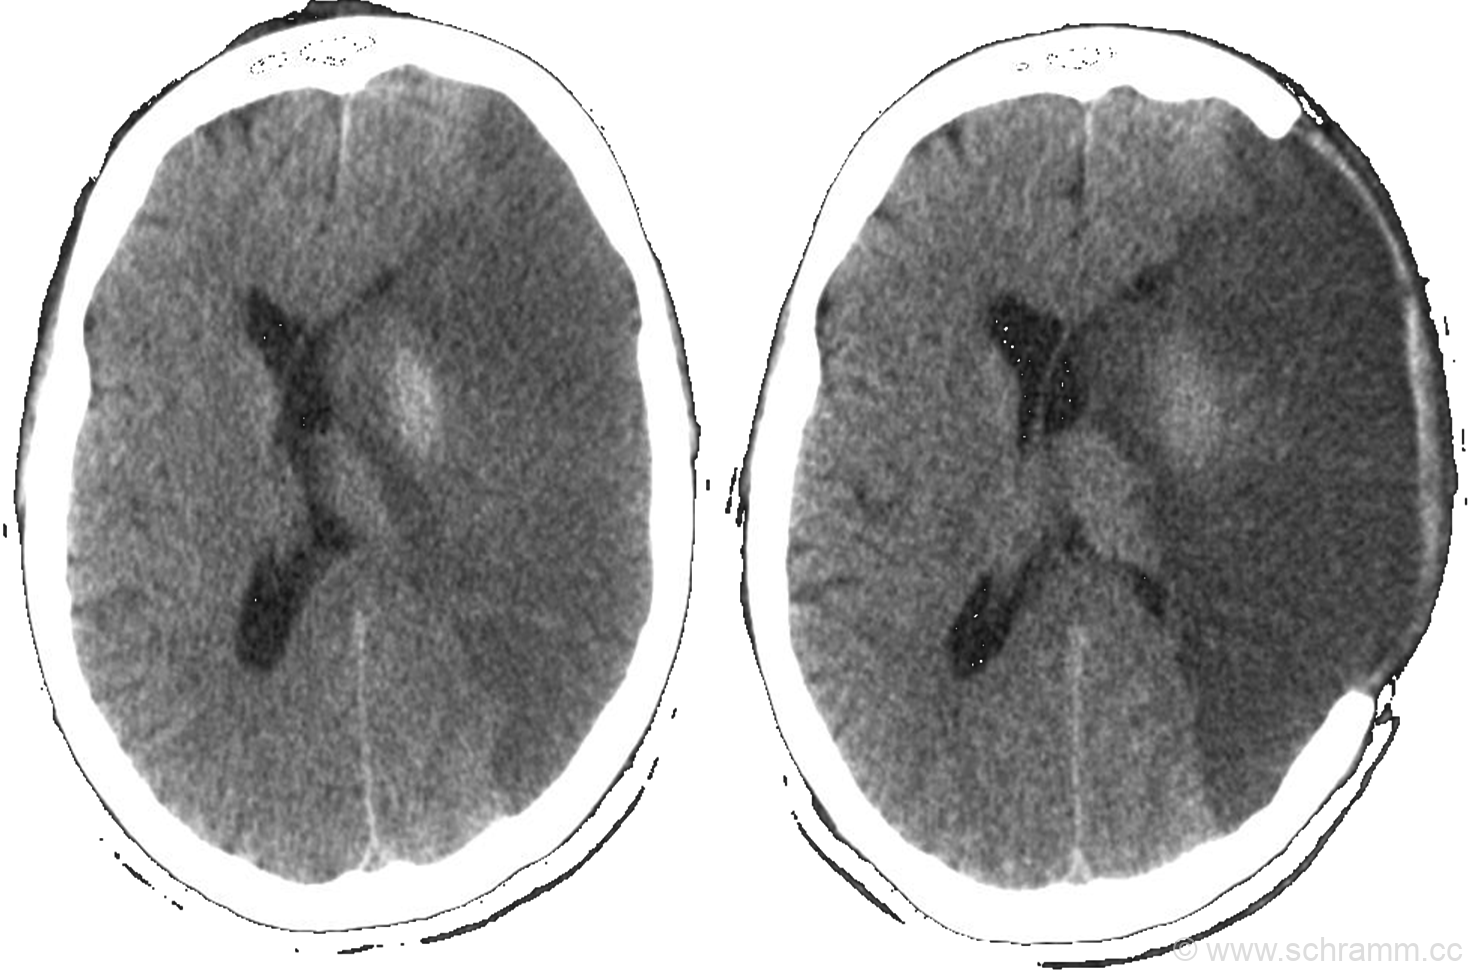

Ischämischer zerebraler Insult

Die sogenannte „time-to-needle“ (Zeitspanne, innerhalb derer eine etwaige Lyse-Behandlung begonnen sein muss) liegt bei maximal 4.5 h nach Eintritt des Schlaganfalls. Vor einer rtPA-Lyse ist eine zerebrale Bildgebung zwingend erforderlich.

Patienten mit akuten embolischen Verschlüssen der proximalen zerebralen Arterien sollten in den ersten 6 h einer mechanischen Rekanalisierung durch intraarterielle neuroradiologische Intervention zugeführt werden.

Patienten über 60 Jahre mit ausgedehnten Infarkten im Stromgebiet der A. cerebri media („Zwei-Drittel-Mediainfarkt“) profitieren von einer osteoklastische Trepanation innerhalb der ersten 48 – 72 h nach Symptombeginn.

Der Begriff Compliance C ist in der Physiologie ein Maß für die Dehnbarkeit von Körperstrukturen. Angewendet auf die intrakranielle Compliance gilt: C=(ΔV)/(ΔICP), wobei ICP der Hirndruck (Intra Cranial Pressure) und V das intrakranielle Volumen ist. Daraus folgt ΔICP=(ΔV)/C. Das bedeutet: Der Hirndruck ICP steigt an wenn das intrakranielle Volumen V (bedingt durch den Mediainfarkt) zunimmt und/oder die intrakranielle Compliance abnimmt.

Eine Erhöhung der intrakraniellen Compliance und damit ein absenken des ICP kann mit einer osteoklastischen Trepanation erreicht werden.